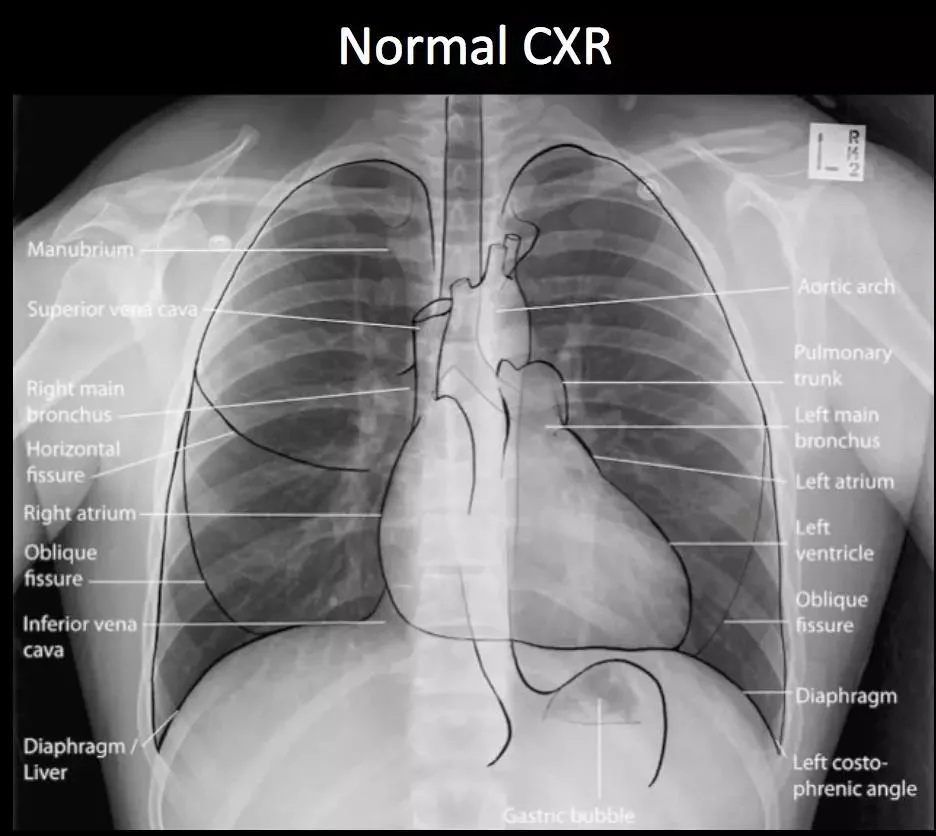

正常胸部X片显示的肺、心脏、血管及胃等正常结构位置